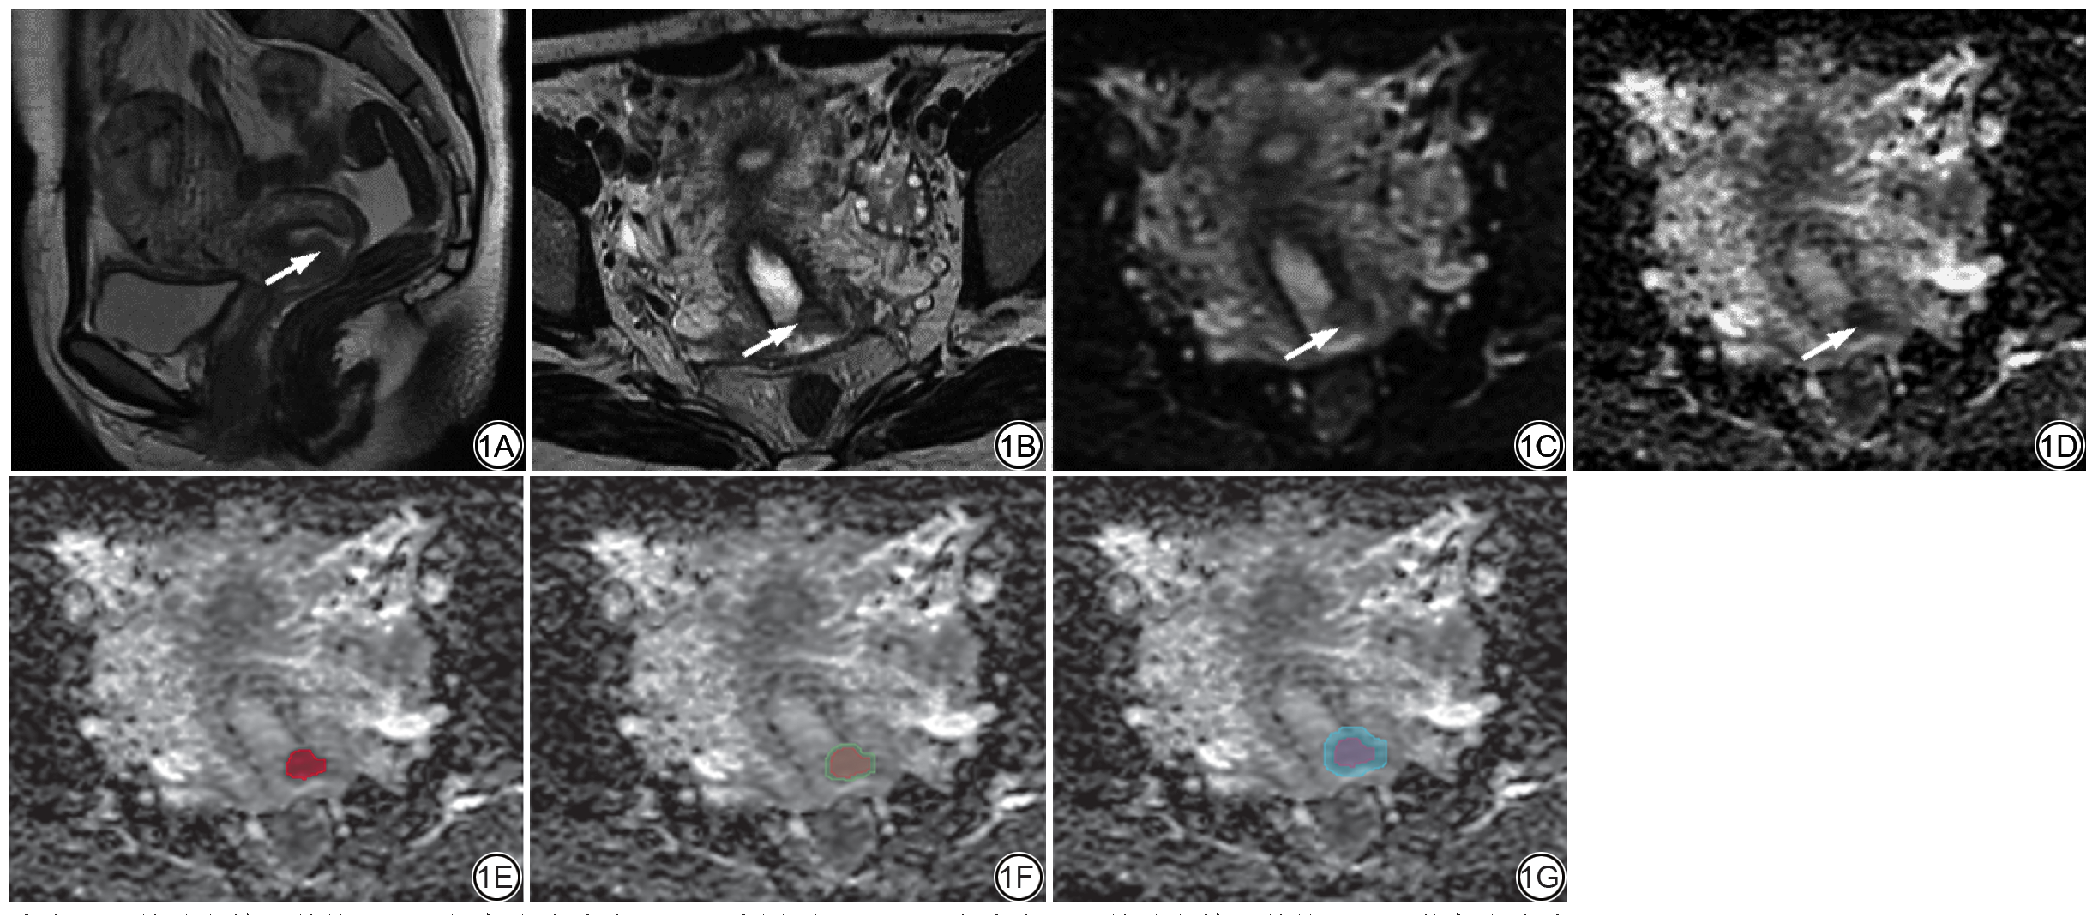

先将DWI原始图像在GE后处理工作站(AW-server workstation, 4.7, GE Healthcare)自动生成ADC图像,再以DICOM格式从工作站导出所有MRI图像。由两位放射科主治医师(分别具有12年和3年腹部MRI诊断经验)独立完成图像分析。为消除偏倚,分析过程中采用盲法设计,医师无法获取患者的临床及病理信息。若两位医师意见不一致,将通过深入讨论或咨询第三位具有30年经验的放射科主任医师意见以达成共识。参照T2WI和DWI图像,使用3D Slicer软件(Slicer5.7.0;https://www.slicer.org/)在ADC轴位图上沿肿瘤最大边界手动逐层勾画瘤内ROI(T2WI均匀中等或稍高信号+DWI高信号+ADC低信号),并注意避开异常信号区域(可能的囊变、出血和坏死区域);瘤周区域的ROI在已确认勾画清楚的瘤内ROI基础上将其边界分别等距外扩2 mm和4 mm得到,注意去除超出宫颈区域的部分。将患者的ADC图像及ROI上传至Fire Voxel软件(版本459;https://firevoxel.org/)自动生成ADC直方图并记录特征参数,包括最小值(ADCmin)、最大值(ADCmax)、均值(ADCmean),1%、5%、10%、25%、50%、75%、90%、95%、99%百分位数(ADC1、ADC5、ADC10、ADC25、ADC50、ADC75、ADC90、ADC95、ADC99),标准差(ADCstdev)、变异系数(ADCcoefofvar)、偏度(ADCskewness)、峰度(ADCkurtosis)和熵(ADCentropy),详见图1

图1  女,28 岁,宫颈癌LVSI 阳性患者,ROI 勾画示意图。1A:T2WI 矢状位图像,病灶呈中等信号,局限于宫颈内;1B:T2WI 轴位图像,病灶为不规则团块状,呈中等信号;1C:DWI 轴位图像,b 值600 mm2/s,病灶为不规则团块状,呈稍高信号;1D:ADC 轴位图像,病灶为不规则团块状,呈低信号;1E:沿肿瘤最大边缘勾画ROI,红色影为瘤内ROI;1F:在瘤内ROI基础上等距外扩2 mm,绿色影为瘤内+2 mm瘤周区ROI;1G:在瘤内ROI基础上等距外扩4 mm,蓝色影为瘤内+4 mm瘤周区ROI。LVSI:淋巴脉管间隙浸润;ROI:感兴趣区;DWI:扩散加权成像;ADC:表观扩散系数。

Fig. 1  ROI sketch of a 28-year-old female with LVSI positive cervical cancer. 1A: Sagittal T2-weighted image, the lesion have a moderate signal and is confined to the cervix; 1B: Axial T2-weighted image, the lesions are irregular clumps with moderate signal; 1C: Sagittal DWI image with b value 600 mm2/s, the lesions are irregular clumps with a slightly high signal; 1D: Sagittal ADC image, the lesions are irregular clumps with low signal; 1E: Outline the ROI along the largest tumor margin, and the red shadow is the ROI of intratumoral area; 1F: Expand outward by 2 mm equidistant on the basis of intratumoral ROI, and the green shadow is the ROI of intratumoral +2 mm periatumoral area; 1G: Expand outward by 4 mm equidistant on the basis of intratumoral ROI, and the blue shadow is the ROI of intratumoral +4 mm periatumoral area. ROI: region of interest; LVSI: lymphovascular space invasion; DWI: diffusion-weighted imaging; ADC: apparent diffusion coefficient.